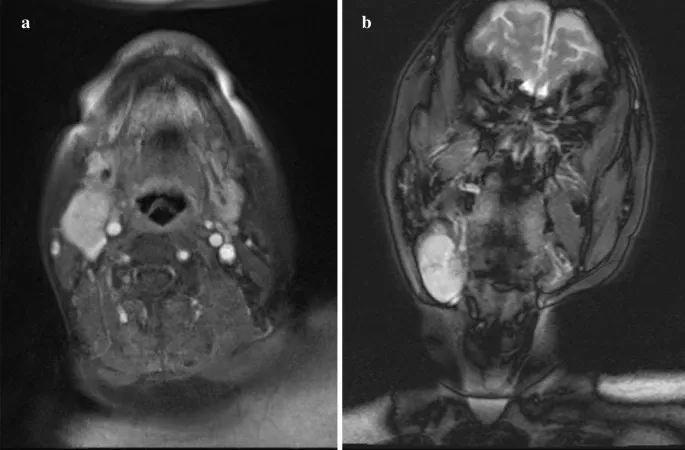

初诊时,右侧下颌下区可触及一个40×30 mm、弹性柔软、可移动的肿块,边界清晰,皮肤颜色健康。无自发性疼痛和压痛。MRI示圆形肿块,边界较清晰,大小为29×24×40 mm,前缘毗邻右侧颌下腺,后深部压迫右侧颈内静脉。边缘很光滑。肿块表现出高信号强度区域,部分伴随为内部的低信号区域。周围组织未见浸润,未见其他明显肿大淋巴结。基于这些发现,强烈怀疑涎腺肿瘤(图1a, b)。

图1. MRI的发现

CT及超声检查均未见异常(图3)。经与本院内分泌外科会诊,2个月行超声引导下细针穿刺活检2次;但在甲状腺中未检测到癌成分。一般来说,隐匿性甲状腺癌的颈部淋巴结转移病例需要全甲状腺切除术。然而,考虑到本例患者PTC进展缓慢、患者年龄、既往有慢性心功能不全、高血压、糖尿病、哮喘病史及整体身体状况,内分泌外科医生未能获得患者的知情同意;因此,对该患者选择密切观察随访。手术后8年,未见颈部肿瘤复发或甲状腺癌大小变化,患者进展良好。

图3. CT结果